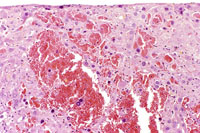

Angiectasis (peliosis hepatis, telangiectasis) is an incidental finding occasionally noted in aging mice. In extensive lesions, atrophy of adjacent hepatocytes may be seen. The lesions consists of dilated sinusoidal spaces lined by normal endothelial cells and filled with blood cells in immersion-fixed specimens. This lesion is occasionally associated with hepatocellular neoplasms. Angiectasis typically consists of smaller blood channels than is seen in hemangiomas. Also, angiectatic vascular channels are often not associated with endothelial cell proliferation as is seen in hemangiomas.

These examples represent high magnification views of angiectasis.